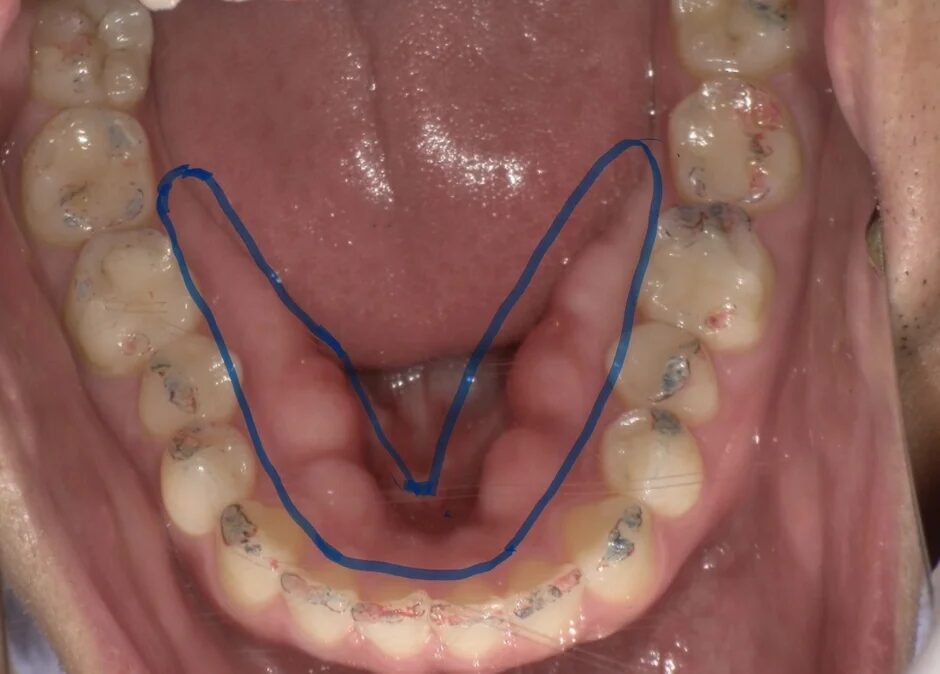

この「食いしばり」が長期間にわたって続くと、顎の骨に強い力が加わり、骨が盛り上がってしまう「骨隆起(こつりゅうき)」という症状が見られることがあります。特に下顎の内側によく見られるのですが、これは、顎にどれくらいの力がかかってきたか、その「力の履歴」を示すサインの一つと考えられています。

40代の男性管理職の方が、「特に悪いところはないと思うが、歯の状態をチェックしてほしい」とあるクリニックを訪れました。口腔内を確認すると、下顎の内側に明らかな骨隆起が認められ、奥歯の咬耗(すり減り)も進行していました。問診で睡眠について尋ねると、「7時間以上は寝るようにしているが、疲れが取れにくい。朝起きた時は、いつも首の後ろが凝っている。」とのことでした。